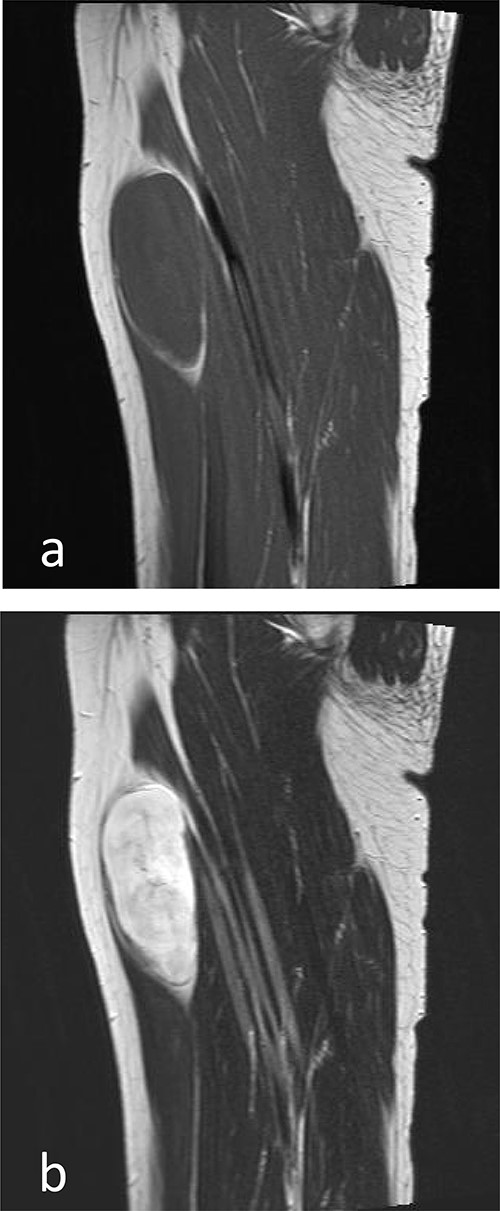

A 44-year-old woman presented to us complaining of a painless, palpable mass in her left thigh slowly growing in size for 10 years (Fig. 1). There were no other symptoms or findings during the physical examination. Physical examination revealed a mass ~9.0 cm in size that was, firm, and had a well-demarcated boundary. Her family and past medical history were unremarkable. Magnetic resonance imaging (MRI) of her left thigh, revealed a discrete, large, well-defined homogenous tumor measuring 8.0 × 3.5 cm in the anteromedial compartment of the thigh, displacing all the muscles of the medial compartment. The tumor showed an isointense signal on T1-weighted images and high-signal intensity on T2-weighted images, suggestive of myxoma (Fig. 2).

MRI imaging (sagittal section). (a) Low-signal intensity to isointense in muscles on T1-weighted images. (b) Hyperintense on T2-weighted images.

Computed tomography showed a well-defined mass that was low-density relative to muscle and enhanced after contrast administration. Findings of neurofibromas on MRI have been reported as typically low-signal intensity to isointense in muscles on TI-weighted MR images and hyperintense on T2-weighted MR images [4, 6]. In this case, similar imaging was finding.